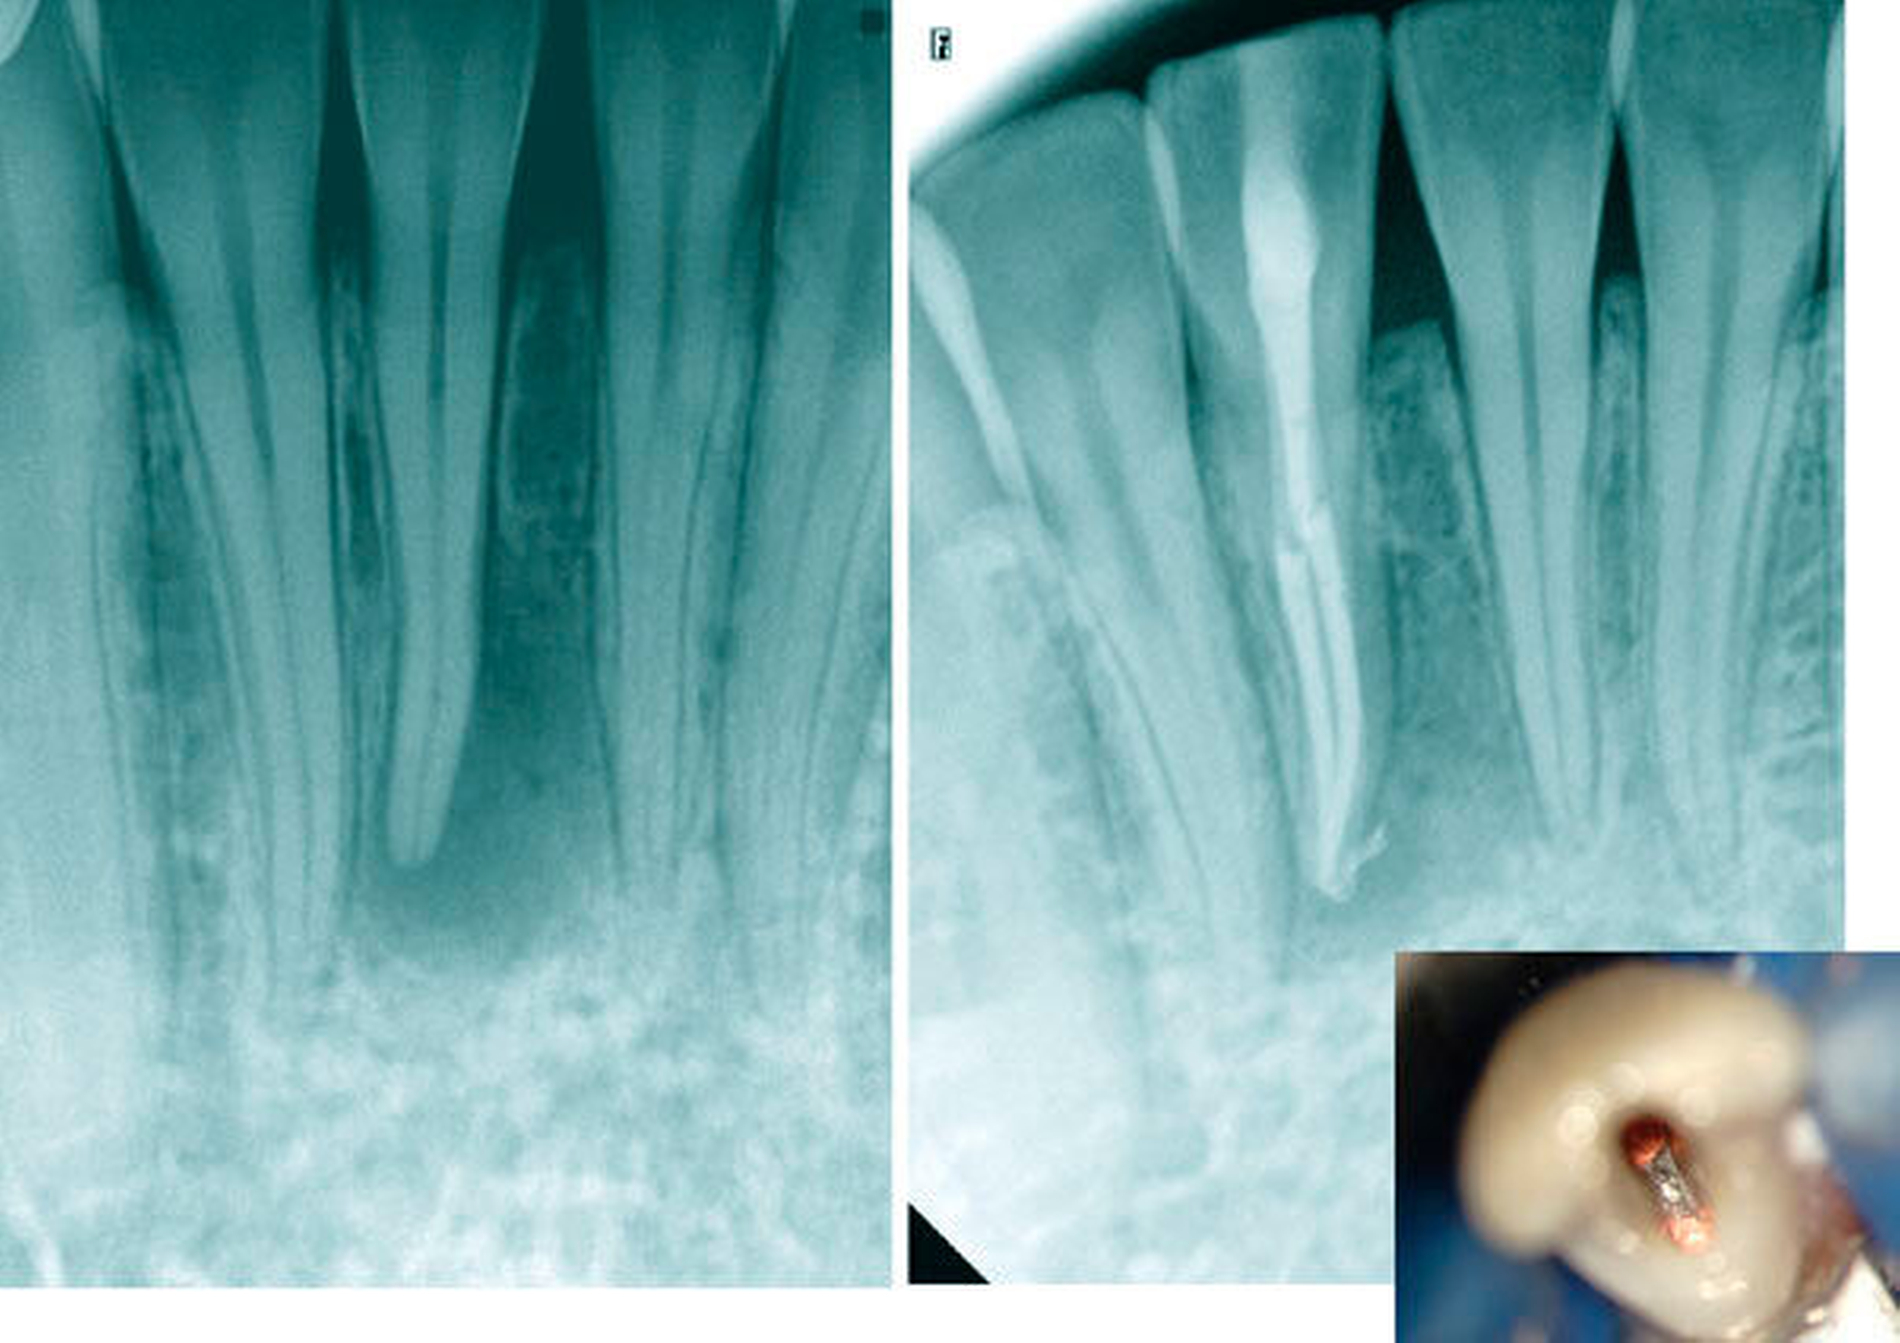

Im jugendlichen Gebiss zählen Zahnhartsubstanzverletzungen infolge eines akuten oder auch chronischen Zahnhartsubstanztraumas zu den größeren Risiken für eine mikrobielle Infektion der Pulpa [Six et al., 2001; Mjör, 2002; Ørstavik & Pitt-Ford, 2008]. Dann können insbesondere bei kariesfreien Schneidezähnen nach Dentinfreilegung Mikroorganismen die weit offenen Dentintubuli penetrieren und eine Pulpanekrose provozieren (Abbildungen 1 und 2).

Häufig ist zu beobachten, dass die lateralen Schneidezähne sowohl in der Wurzellänge als auch in der Breite größer sind als die zentralen und entlang der Wurzelfläche auf der mesialen und der distalen Seite eine Einziehung unterschiedlicher Tiefe aufweisen [Hollaender, 1870; Schumacher, 1985]. Je ausgeprägter diese ausgebildet ist, desto sicherer liegt innerhalb der Wurzel eine Aufteilung der Wurzelkanäle vor. Das Verhältnis von Länge und Breite der Zahnkrone kann als ein Hinweis auf ein mehrkanaliges Wurzelkanalsystem genutzt werden. Demnach lagen bei zunehmender bukko-labialer Ausdehnung der Zahnkrone in 70 Prozent der Fälle zwei Wurzelkanäle vor [Warren&Laws, 1981]. Im Einzelfall können bis zu drei Wurzelkanäle vorkommen. Im Rahmen der röntgenologischen Diagnostik kann eine Kontinuitätsunterbrechung des Wurzelkanalverlaufs als ein sicherer Hinweis auf eine Aufteilung der Wurzelkanäle gewertet werden (Abbildungen 9a bis 9c).

Die geringe Größe der klinischen Zahnkrone mit maximal 4 bis 5 mm Breite oder eine gedrehte oder gekippte Zahnstellung allein sind große klinische Herausforderungen, das Wurzelkanalsystem im Fall einer endodontischen Behandlung vollständig darstellen zu können. Die tiefen Aufteilungen als Folge einer Dentinbrücke lassen sich ohne Nutzung eines Dentalmikroskops nur mit erheblichem Zahnhartsubstanzverlust darstellen, so dass der Langzeiterhalt des Zahnes mit der erhöhten Gefahr einer Vertikalfraktur kompromittiert wird. Bei alters- oder reizbedingten Obliterationen des Wurzelkanalsystems erhöht sich darüber hinaus das Risiko einer lateralen Wurzelperforation oder Instrumentenfraktur [Kvinnsland, 1989] (Abbildungen 16a und 16b).